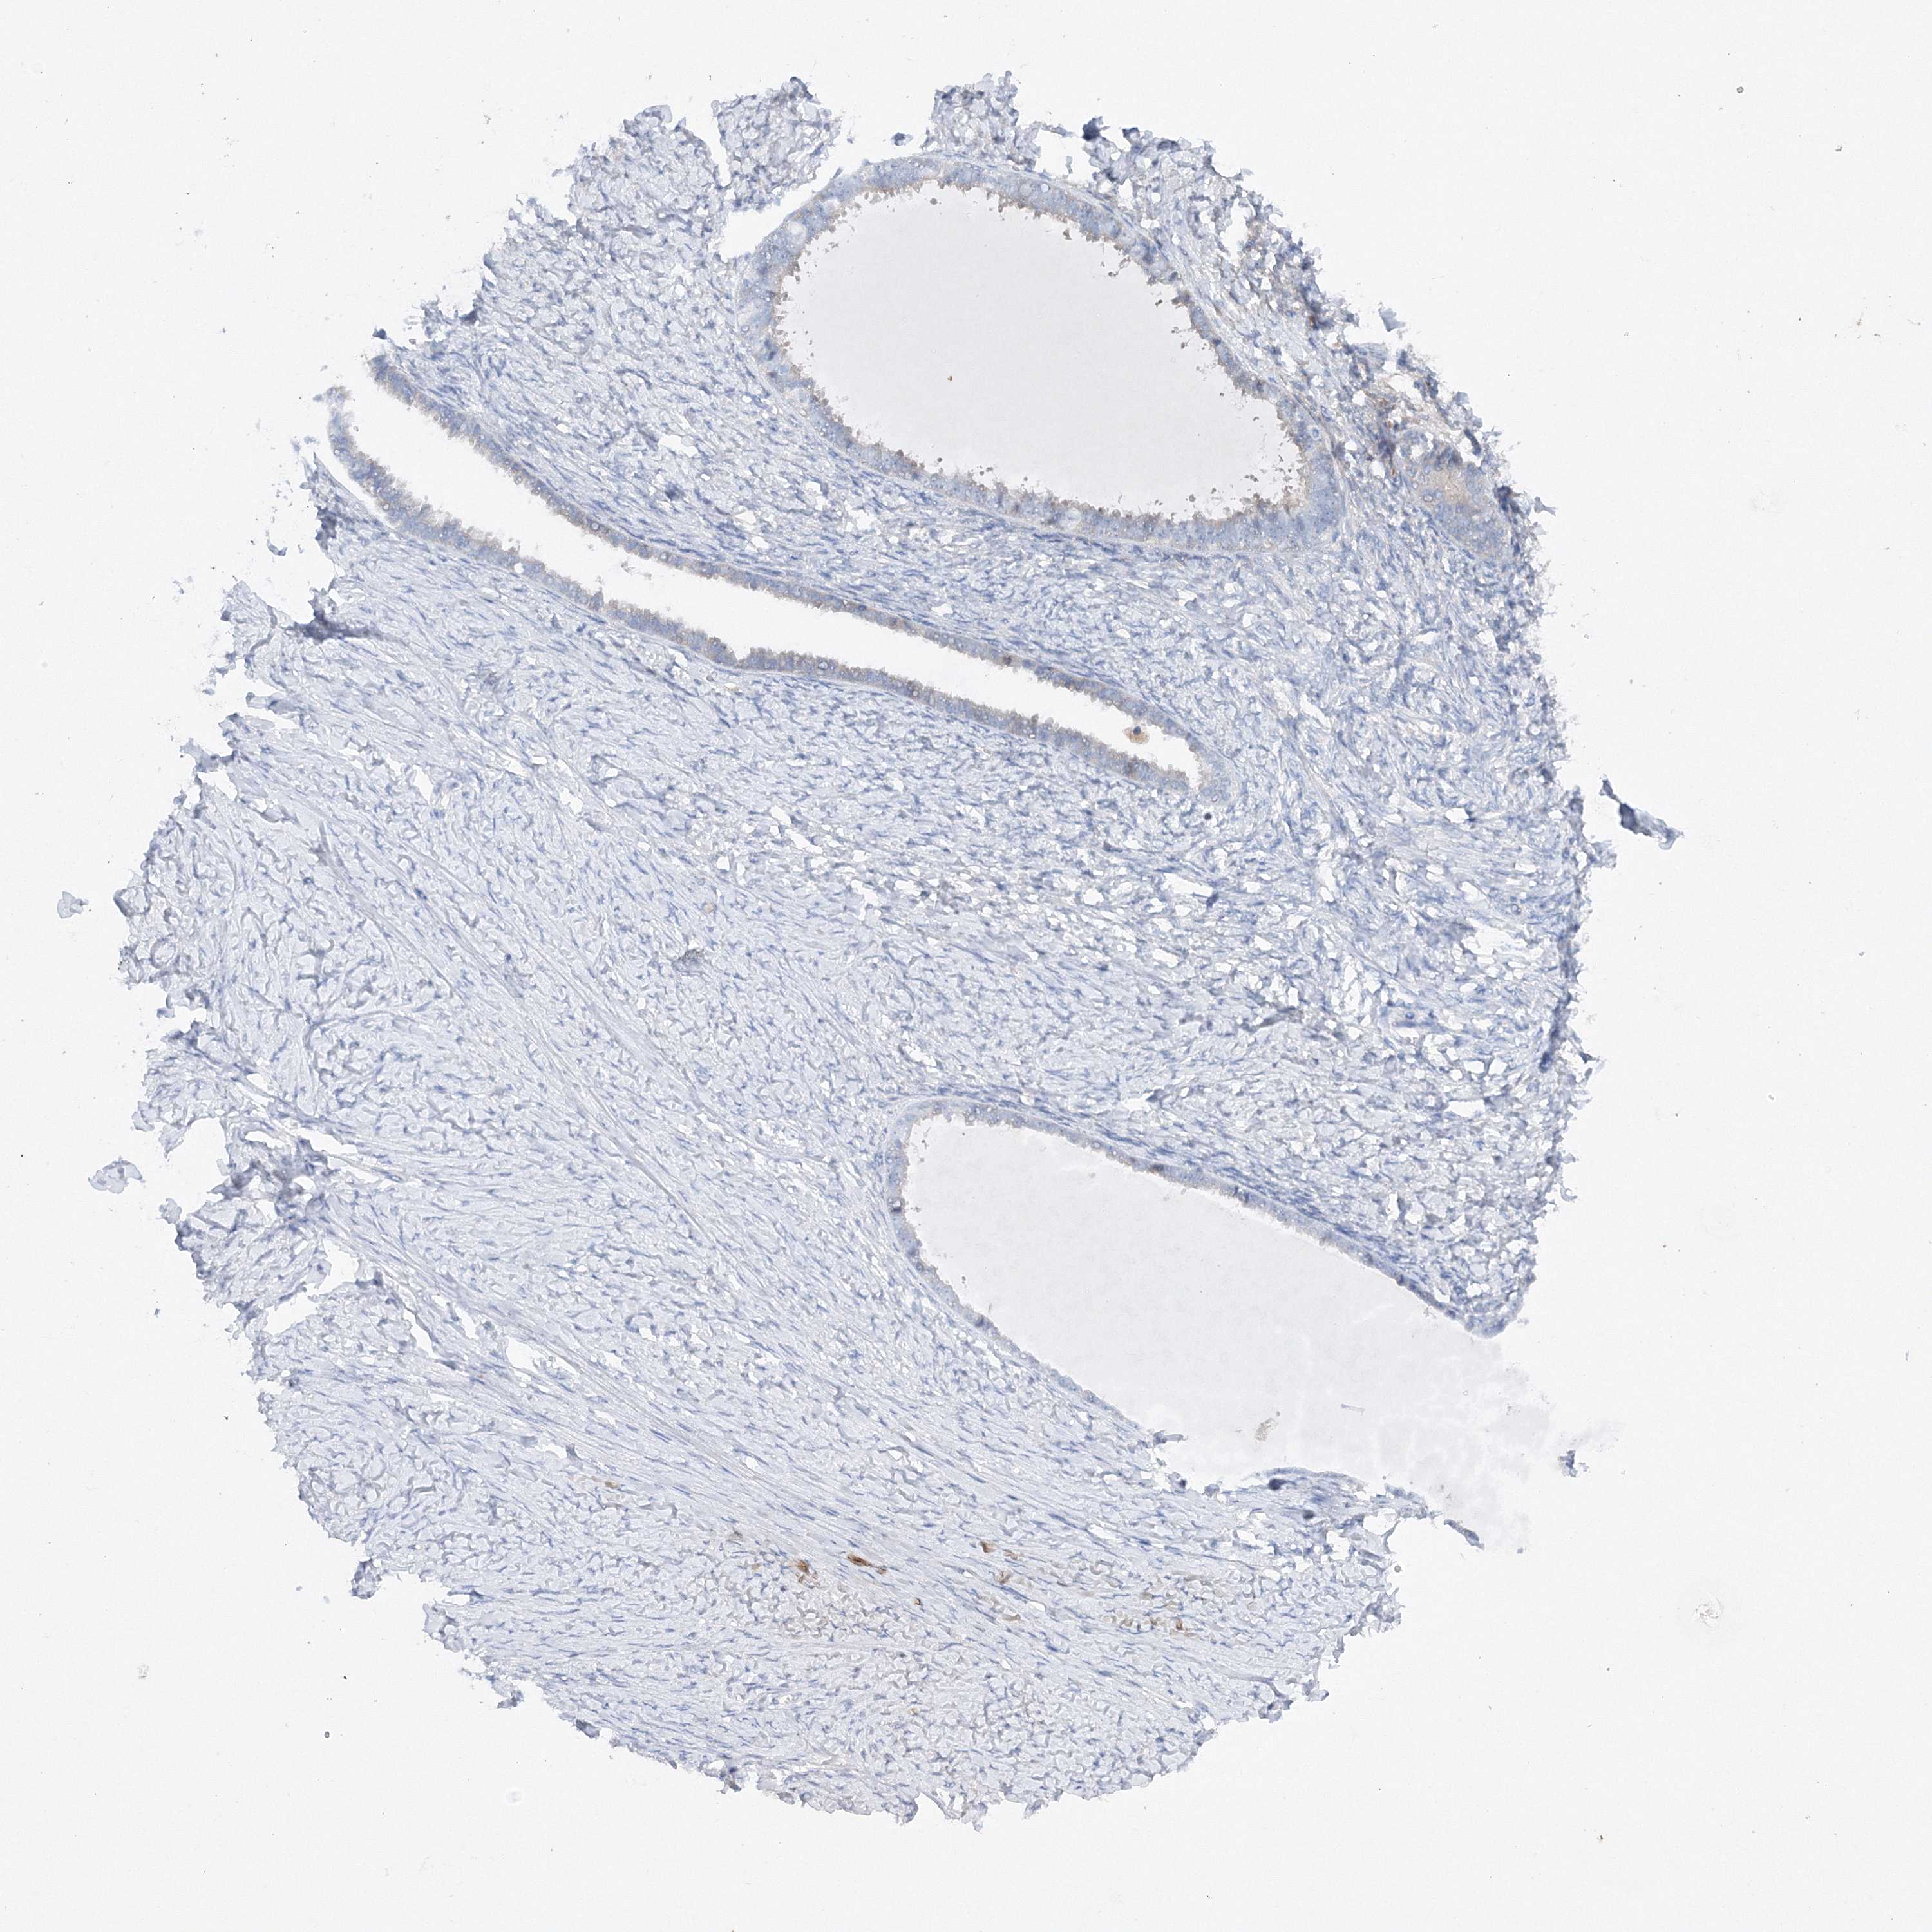

OVARIAN CANCER - Protein expressioni

A mouse-over function shows sample information and annotation data. Click on an image to view it in a full screen mode. Samples can be filtered based on level of antibody staining by selecting one or several of the following categories: high, medium, low and not detected. The assay and annotation is described here.

Note that samples used for immunohistochemistry by the Human Protein Atlas do not correspond to samples in the TCGA dataset.

Antibody stainingi

Antibody staining in the annotated cell types in the current human tissue is reported as not detected, low, medium, or high, based on conventional immunohistochemistry profiling in selected tissues. This score is based on the combination of the staining intensity and fraction of stained cells.

Each image is clickable and will lead to virtual microscopy that enables deeper exploration of all samples and also displays staining intensity scores, fraction scores and subcellular localization as well as patient and tissue information for each sample.

Antibody HPA035937

Staining

High

Medium

Low

Not detected

Intensity

Strong

Moderate

Weak

Negative

Quantity

>75%

75%-25%

<25%

None

Location

Nuclear

Cytoplasmic/membranous

Cytoplasmic/membranous,nuclear

Cystadenocarcinoma, serous, NOS

Carcinoma, endometroid

Cystadenocarcinoma, mucinous, NOS

Carcinoma, NOS